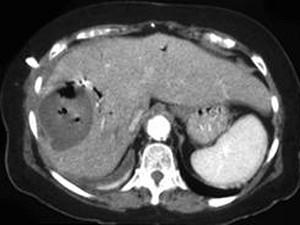

问题 男,48岁,寒战高热,右上腹痛一天,CT检查如图所示,最可能的诊断是 ( )

选项 A、肝错构瘤 B、肝转移瘤 C、肝脓肿 D、胆管细胞癌 E、原发性肝癌 单选题

答案 C